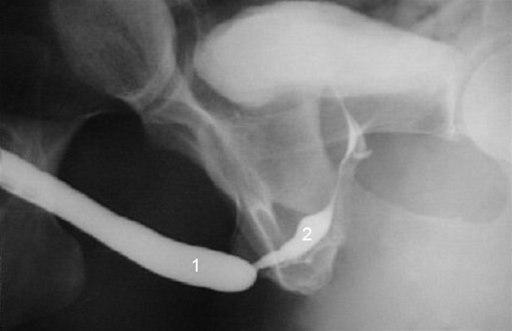

Innsnevring i urinrøret (1 - ytre del)Innsnevring av urinrøret betegnes på fagspråket uretrastriktur (uretra = urinrør, striktur = trangt parti). Urinrøret går fra urinblæren og ut.

En innsnevring av urinrøret kan være lokalisert i ytre del av urinrøret eller i indre del av urinrøret (inn mot blæren). De fleste innsnevringer befinner seg i ytre del av urinrøret som innbefatter urinrørets passasje gjennom penis og penisroten (bulbus).

For å kunne stadfeste diagnosen bør det gjøres røntgenundersøkelse der røntgenkontrast sprøytes inn i urinrøret, eller det gjøres cystoskopi hvor et bøyelig skop med lyskilde føres inn i urinrøret og legen (urologen) kan påvise hvor innsnevringen er. Mange menn er motvillige til å gjennomgå en urologisk undersøkelse på grunn av frykt for smerter eller seksuelle forstyrrelser, men det er liten grunn for slike bekymringer.